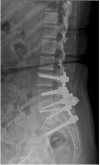

Sacropelvic is a complex junctional area owing to the complex regional anatomy and higher biomechanical stress. However extension of construct is indicated in cases with complex deformities, high grade spondylolisthesis, and complex fractures. The challenges remain which includes pseudoarthrosis and fixation failures. The fixation techniques have constantly evolved over time with better results with iliac screws and S2-alar-iliac screws. This article gives background on evolution, biomechanics, and recent update of use of robotics for sacropelvic fixation.